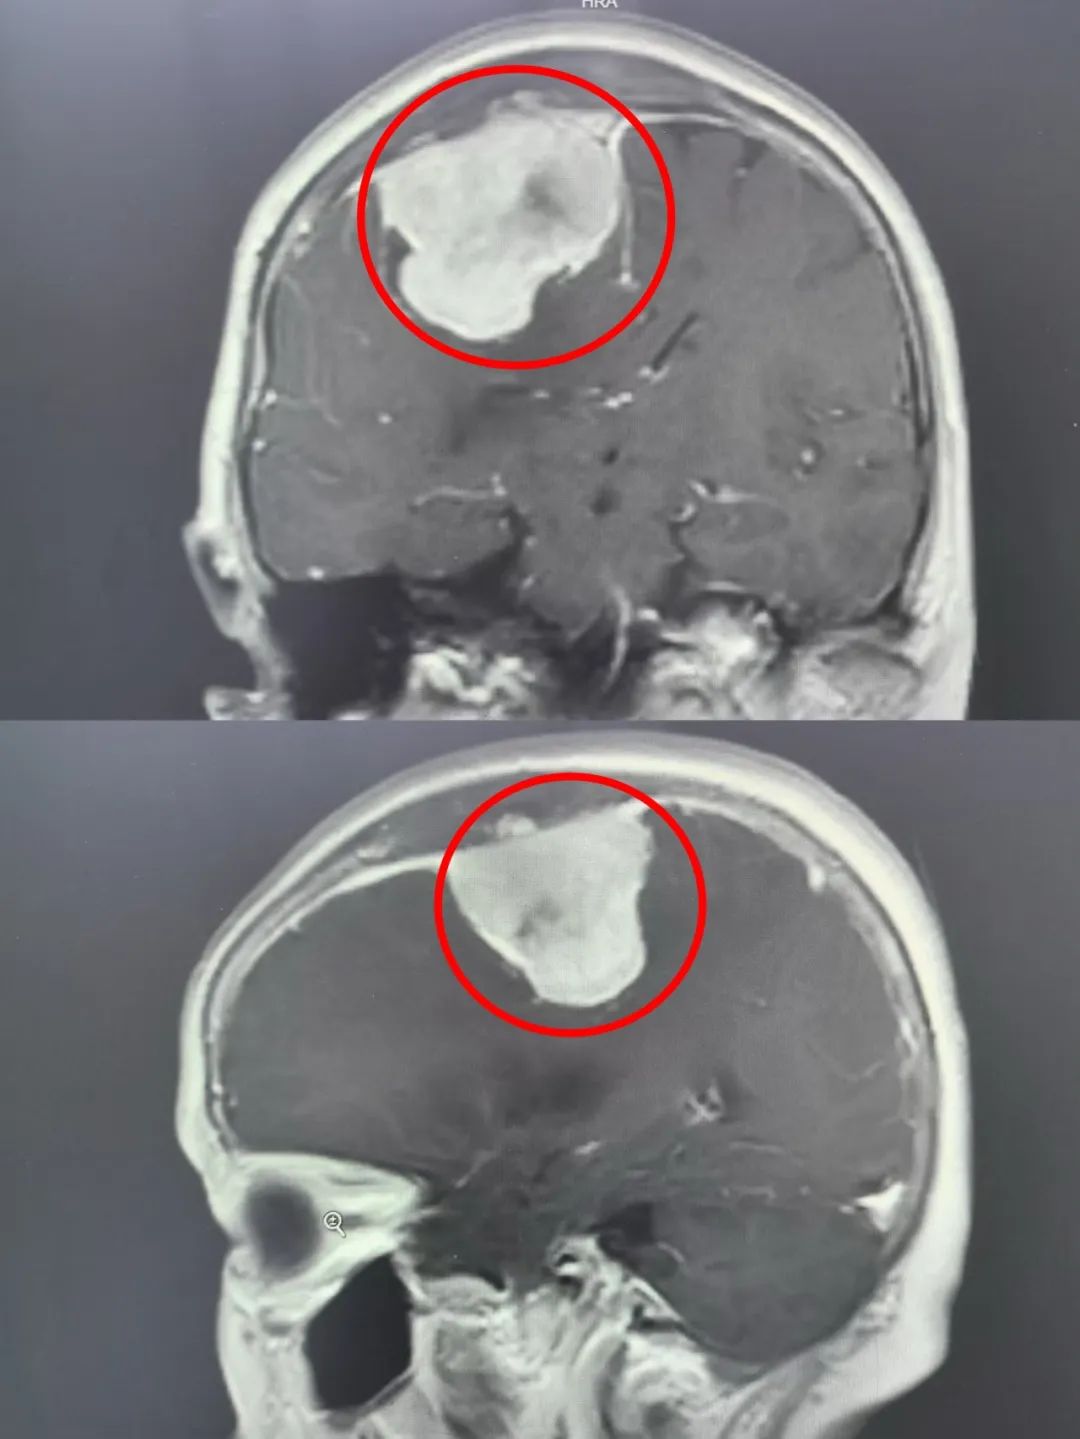

影像检查却发现:

大脑里面藏着一颗

“鸡蛋”大小的肿瘤

上矢状中段窦旁大脑膜瘤

脑膜瘤是大脑内常见的原发性肿瘤。它生长缓慢,大多都是良性,隐蔽性强,多数生长到很大才会被发现。上矢状窦是位于大脑最顶端粗大的静脉血管上矢状窦旁脑膜瘤(简称窦旁脑膜瘤)就是来源于很薄的上矢状窦壁的脑膜瘤。上矢状中段窦旁大的脑膜瘤通过开刀手术治疗,极容易引起致命性大出血,或永久性偏瘫,手术风险很大。肿瘤周围都是“惹不起”重要的结构,难度可想而知。

“杨婆婆颅内的脑膜瘤直径达到5cm,已经很大了,像一块吸饱水的海绵,紧紧黏附在上矢状窦侧壁。这个位置的肿瘤就像攀附在悬崖上的藤蔓,既要完整剥离,又不能扯断‘悬崖’结构,极具挑战。完整切除肿瘤,能最大限度的减少术中出血,但又对手术技巧提出更高要求。